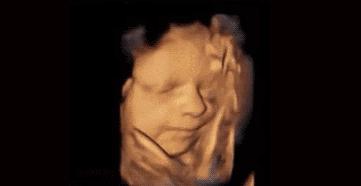

菌菌告诉你,小家伙不仅会做各种动作,表情更是丰富的不得了。

小脑袋一晃一晃的,我不答应,我不高兴,我要吃肉肉……

咦,妈妈在外面跟我说话,嘟嘴卖个萌先。

哈哈,妈妈肯定是被我萌到了,我都听到她的笑声了。